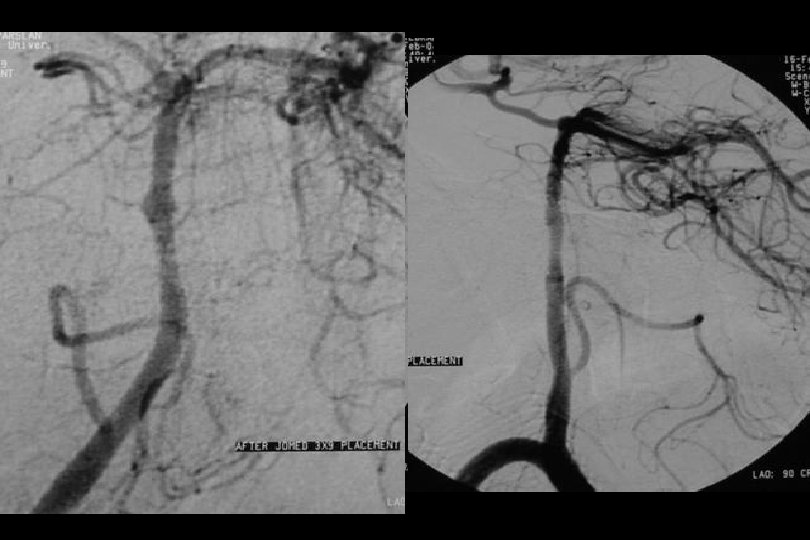

3 yıl kontrol

2. Yıl kontrol

Balonla açılan stentler Avantaj / Dezavantajlar • Damar içinde daha iyi açılırlar ve damar duvarına daha iyi yapışırlar • İlaç salınımlı tipleri • Restenoz oranları nispeten düşüktür. Mawad et al İlaç salınımlı olmayanlar: %8 İlaç salınımlı: %5 SSYLVIA çalışması (VA ostial stenozlar dahil olmasına rağmen): restenoz oranı %34 • Stent açılması daha travmatik • İntrakraniyal damarlarda navigasyon daha zor; exchange tel kullanımı gerektirir (distal damar perforasyon riski). . .